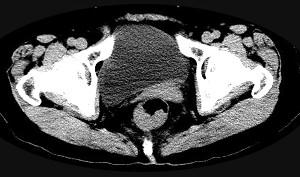

问题 男,56岁,排便形状改变,便不尽感,CT检查如图所示,下列说法正确的是 ( )

选项 A、此为直肠息肉 B、此为直肠癌 C、其表面光滑,边界清楚 D、肠腔未见狭窄 E、肠壁上有蒂状新生物

答案 B